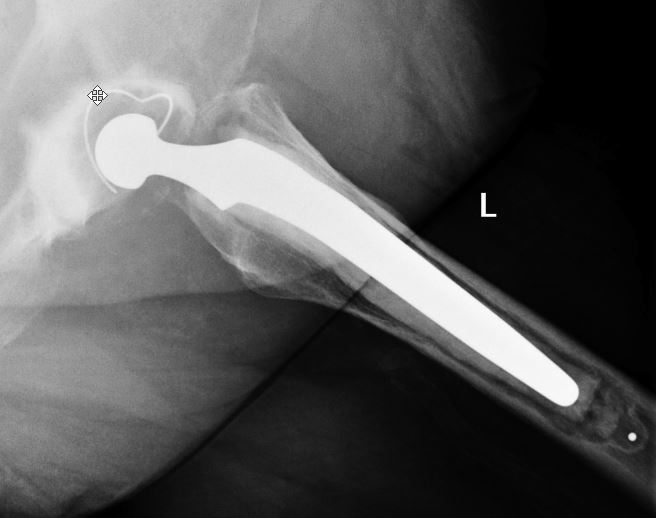

Classification: Dorr

1. What is the Dorr classification?

A

Dorr classification

• is used to evaluate the quality of proximal femoral bone according to radiographic, biochemical and histologic data.

• where it describes the relationship of the diameter of proximal femoral canal relative to diameter of the femoral diaphysis.

• by measuring the ratio between the canal diameter of the femoral diaphysis 10 cm distal to mid point of the Lesser Trochanter and canal diameter at mid point of the Lesser Trochanter.

• and as such divide into 3 types, which is then used as a guide indications for cemented or uncemented femoral component fixation.

• Type A: ratio <0.5, thick bone cortices in AP and lateral views with narrow canal, referred to as “champagne flute”, commonly found in younger patients. Femoral fixation type: Uncemented.

• Type B: ratio 0.5 to 0.75, thining of cortices seen typically at medial and posterior on lateral view, resulting in a widened residual funnel shape canal. Femoral fixation type: Uncemented.

• Type C: >0.75, thinning of cortices on both views, stovepipe shape. Femoral fixation type: Cemented.